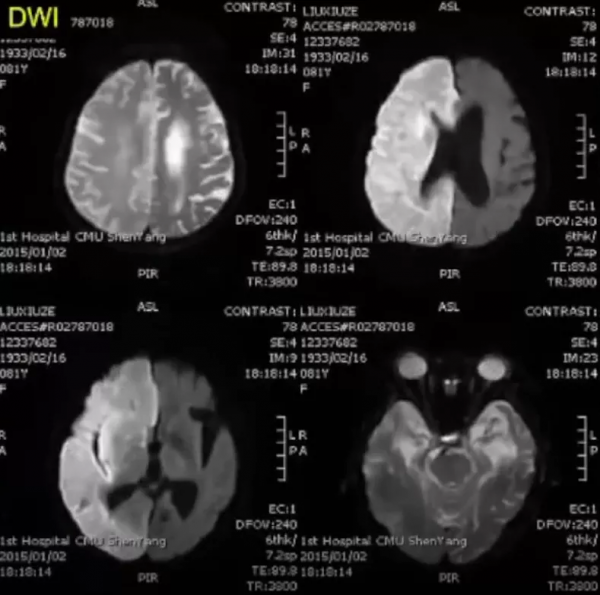

2015年2月,顱腦MRI+DWI示右側大腦半球可見瀰漫性長T1、長T2訊號,腦組織腫脹,腦溝變淺;左側腦室旁可見片狀長T2訊號病灶。

2015年2月,右側大腦半球瀰漫性病灶,DWI呈彌散受限高訊號,ADC呈低訊號。

6、顱腦MRI+DWI可見右側大腦半球瀰漫性長T2訊號、DWI高訊號病灶。